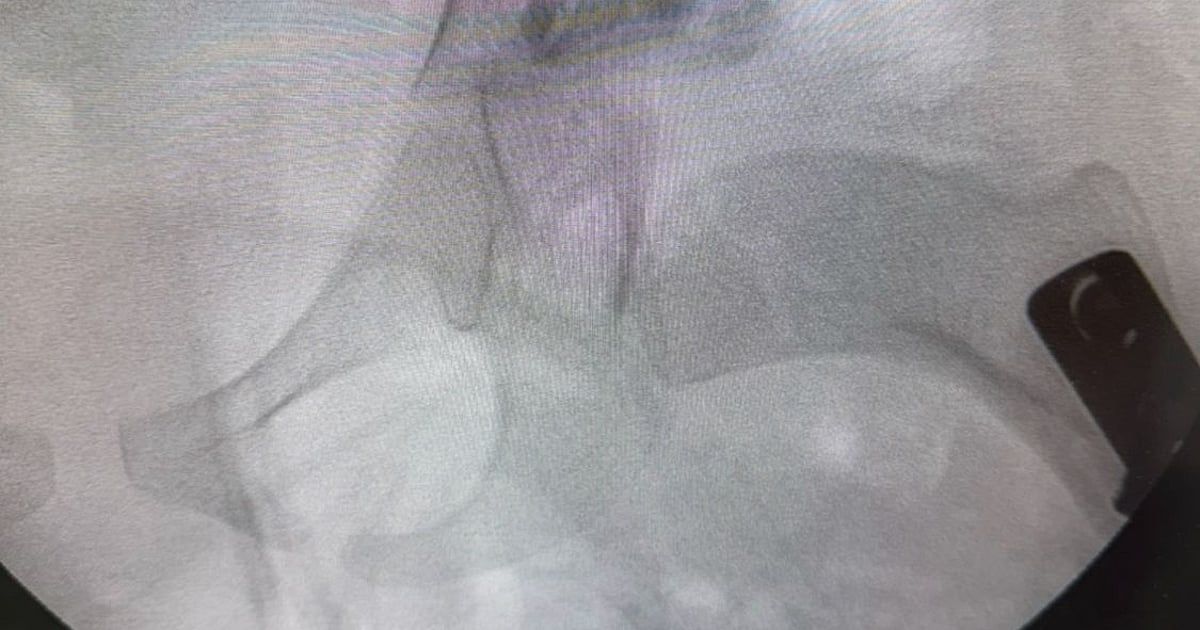

في إنجاز طبي لافت، نجح فريق طبي من قسم جراحة العظام في مستشفى المانع بالخبر، بقيادة استشاري جراحة عظام الأطفال الدكتور إبراهيم البراهيم، في إجراء عملية دقيقة لطفلة تبلغ من العمر أربع سنوات كانت تعاني من خلع ولادي مزدوج في مفصل الورك وتشوه في رأس عظمة الفخذ مع انحراف في عنق العظمة بالجهتين.

وأوضح الفريق الطبي أن هذا النوع من العمليات يُجرى عادة في عمر السنة، ما يجعل نجاحها في هذا العمر المتأخر إنجازًا طبيًا يُحسب للمستشفى وللكادر الجراحي بفضل خبرتهم وكفاءتهم العالية.

وأكدت إدارة المستشفى أن العملية تكللت بالنجاح الكامل، حيث استعادت الطفلة عافيتها بفضل التنسيق المتكامل بين أقسام جراحة العظام والتخدير والتمريض.